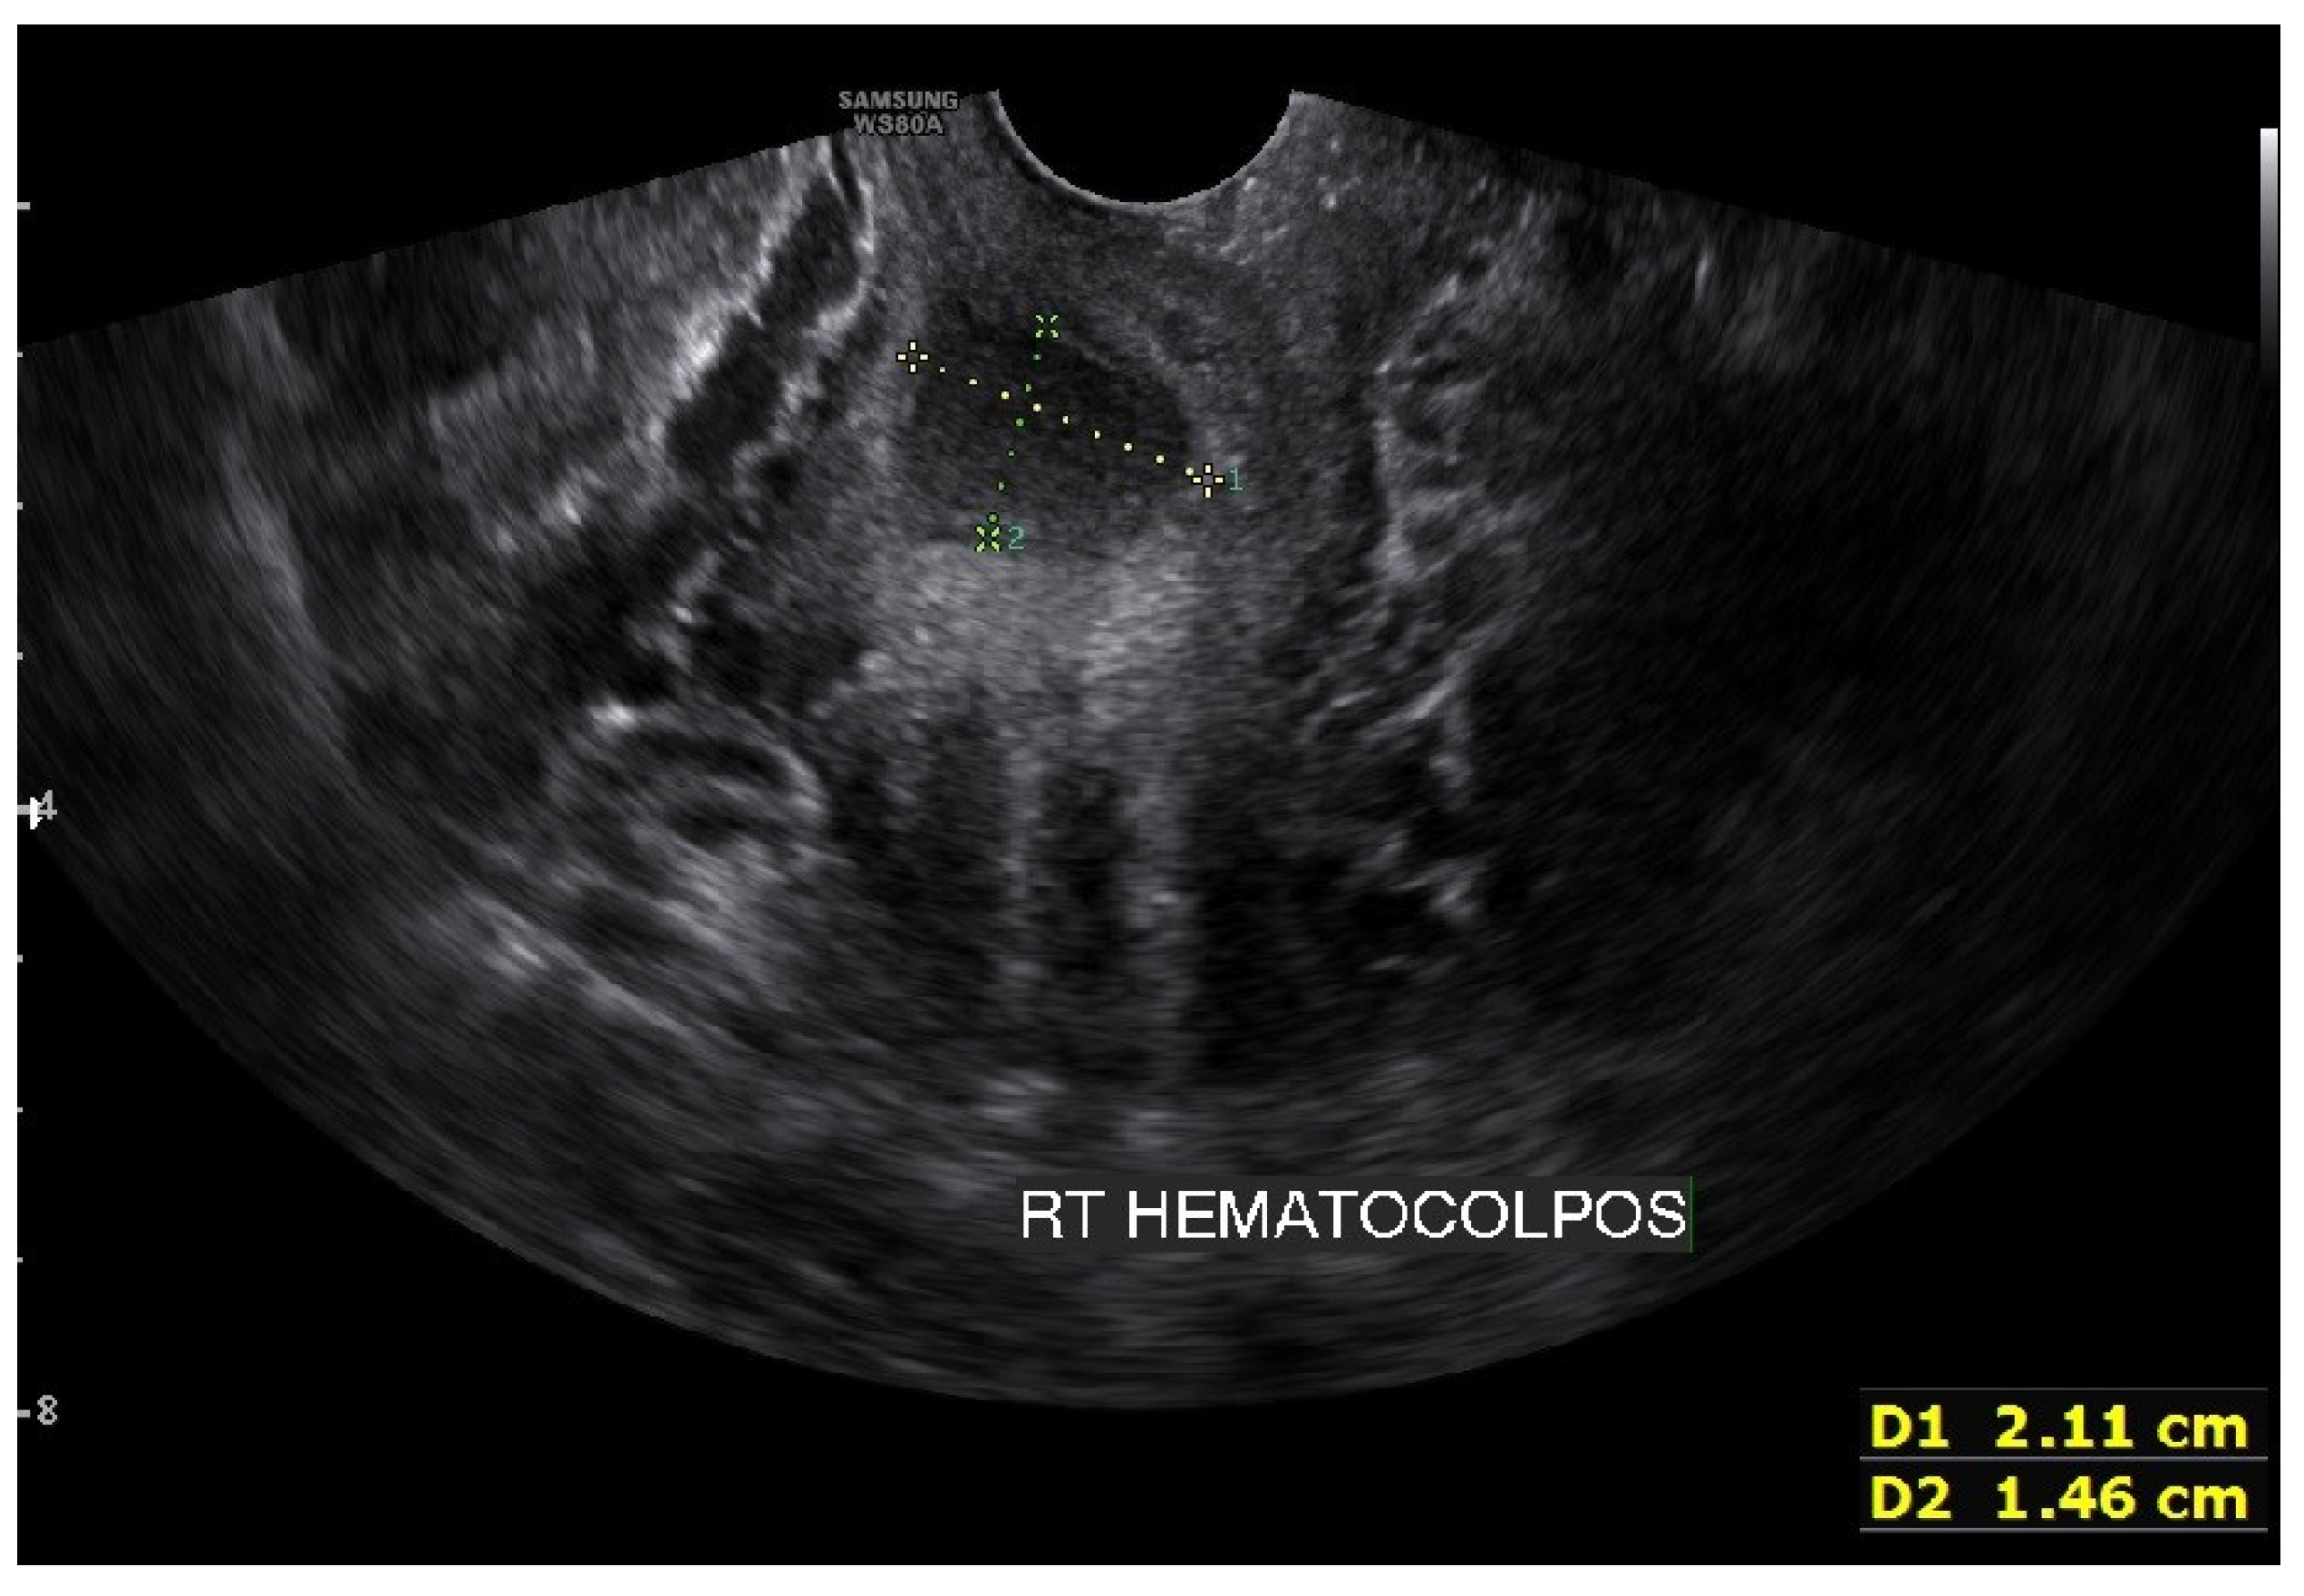

On the abdominopelvic CT image taken at the ER, we noticed she had HWW syndrome (right side hemi-vagina and right kidney agenesis) with acute pyelonephritis (APN) of the left kkidne (Figure 3a,b). After admission, transvaginal USG (Figure 4) and pelvic MRI (Figure 5a–c) were performed. We planned to perform the vaginal wall resection surgery on the next menstrual period as she needed antibiotics treatment for the APN, and the amount of hematocolpos was not so extensive that we could not clearly identify the bulging vaginal wall.

Figure 4. Transvaginal ultrasonogram image showing approximately 21 mm × 15 mm of fluid collection in the right side obstructed hemivagina. This suggested hematocolpos on the right side was too small and made it difficult to operate on the first visit.